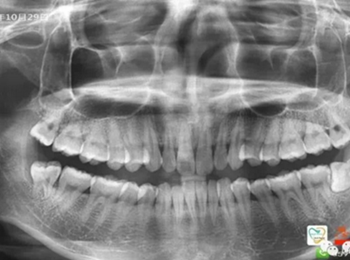

由于智齒的生長位置特殊,導致了拔除難易不同,如智齒出現(xiàn)橫著長或者靠近牙神經的話,則難度會較高,一般人只需拍個口腔全景片,但相對于智齒靠近神經管的情況,還可能需要拍CT,這都很考驗牙醫(yī)的技術。

拔牙非小事,請不要拿成本衡量牙醫(yī)的價值!

下面這兩張圖,據(jù)說拔牙費時1.5小時,收費14000元。